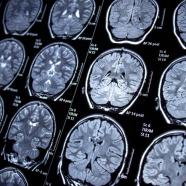

A 3D Camera for the Brain: The Simplified Science of MRI

Have you ever dreamed of having Superman’s power of “X-Ray Vision,” or the ability to see through solid objects? While it is uncertain if this superpower was their motivation, medical researchers and physical scientists in the 1970s were able to turn this dream into a sort of reality with the invention of the MRI scan [1].

MRI is a non-invasive method used by physicians and scientists to gain insight into the structure and function of internal organs, often to help determine the root of unexplained symptoms like chronic headaches or seizures. This procedure can sound pretty scary if you’ve never had one before, and it is common to have questions about not only how safe of a procedure it is, but what exactly is happening in the body during an MRI. Let’s talk about it!

MRI stands for magnetic resonance imaging, which means that the machine uses magnetic fields and the principle of resonance (a type of atomic spinning, detailed later) to create an image. Simply put, an MRI scanner is a magnet – a big, loud, donut-shaped magnet (Figure 1). Each MRI scanner uses a specific magnetic field, the strength of which is measured in units called “Teslas” (often just labeled as “T”). Stronger MRI scanners have an increased Tesla range, and thus can parse out smaller differences in resonance – so the higher the Tesla of the scanner, the better the image resolution. Typically, clinical MRI scanners come in 1.5T or 3T variations, with the world’s most powerful human scanner to date at 11.7T [3]. This machine acts as a 3D camera, and takes pictures of soft tissues like the brain or the spinal cord that are not visible in other forms of imaging when bones get in the way, such as a traditional X-ray scan. Perhaps Superman’s power should be renamed “MRI Vision.”